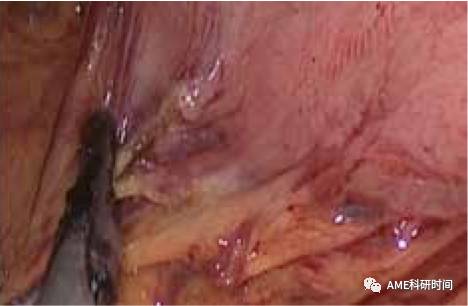

5改良反穿刺法:在操作反穿刺法时,在镜下从中心杆取下穿刺头有一定难度,故设计了改良法。腹腔外,用7号丝线在中心杆上打结10余个,同侧方置入法置入钉钻头及打开食管,距开口近端0.5 cm处食管前壁戳孔,引出丝线,由丝线引出中心杆,并将钉钻头置入食管内,直线切割闭合器紧贴穿中心杆闭合断离食管(如图19-24)。

管型吻合器怎么用完全腹腔镜下全胃切除术后的消化道重建——7种食管空肠吻合方法_https://www.jmylbn.com_新闻资讯_第19张

图19 7#丝线连接钉钻头

管型吻合器怎么用完全腹腔镜下全胃切除术后的消化道重建——7种食管空肠吻合方法_https://www.jmylbn.com_新闻资讯_第20张

图20 打开食管前壁

管型吻合器怎么用完全腹腔镜下全胃切除术后的消化道重建——7种食管空肠吻合方法_https://www.jmylbn.com_新闻资讯_第21张

图21 牵入中心杆

管型吻合器怎么用完全腹腔镜下全胃切除术后的消化道重建——7种食管空肠吻合方法_https://www.jmylbn.com_新闻资讯_第22张

图22 置入钉钻头

管型吻合器怎么用完全腹腔镜下全胃切除术后的消化道重建——7种食管空肠吻合方法_https://www.jmylbn.com_新闻资讯_第23张

图23 断离食管

管型吻合器怎么用完全腹腔镜下全胃切除术后的消化道重建——7种食管空肠吻合方法_https://www.jmylbn.com_新闻资讯_第24张

图24 置入后效果